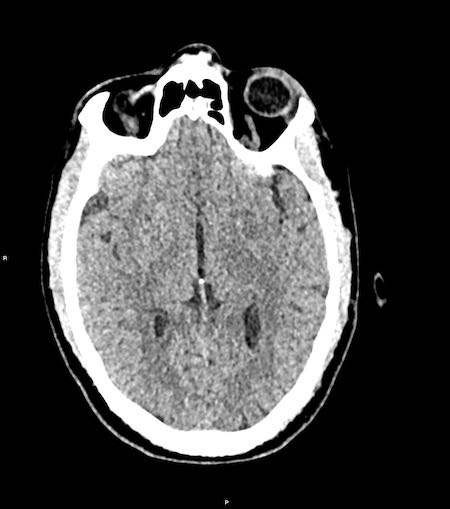

Đây là trường hợp tụ máu dưới màng cứng đồng tỷ trọng rất khó phát hiện (các mũi tên).

Lưu ý rằng ở mức cắt cao hơn có tụ máu dưới màng cứng hai bên.

Tụ máu dưới màng cứng có thể lan dọc theo liềm não và lều tiểu não như trong trường hợp này.

Các hình ảnh cho thấy máu tăng tỷ trọng trong khoang dưới nhện của rãnh Sylvius (mũi tên vàng).

Lưu ý xuất huyết dưới da đầu vùng chẩm phải (mũi tên xanh).

Đây là dạng tổn thương chấn thương kiểu coup-contrecoup.

Đây là một trường hợp chấn thương kiểu coup-contrecoup khác với các xuất huyết dập não và tụ máu dưới màng cứng ở thùy trán trái gần nền sọ (mũi tên đỏ).

Có xuất huyết dưới nhện bên phải kèm gãy xương đỉnh (mũi tên vàng).